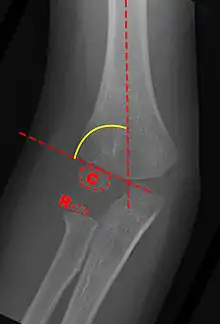

Baumann's Angle

Carrying angle can be evaluated through AP view of the elbow by looking at the Baumann's angle.[3] There are two definitions of Bowmann's angle:

The first definition of Baumann's angle is an angle between a line parallel to the longitudinal axis of the humeral shaft and a line drawn along the lateral epicondyle.

Another definition of Baumann's angle is also known as the humeral-capitellar angle. It is the angle between the line perpendicular to the long axis of the humerus and the growth plate of the lateral condyle. Reported normal values for Baumann's angle range between 9 and 26°.[7] An angle of more than 10° is regarded as acceptable.[7]